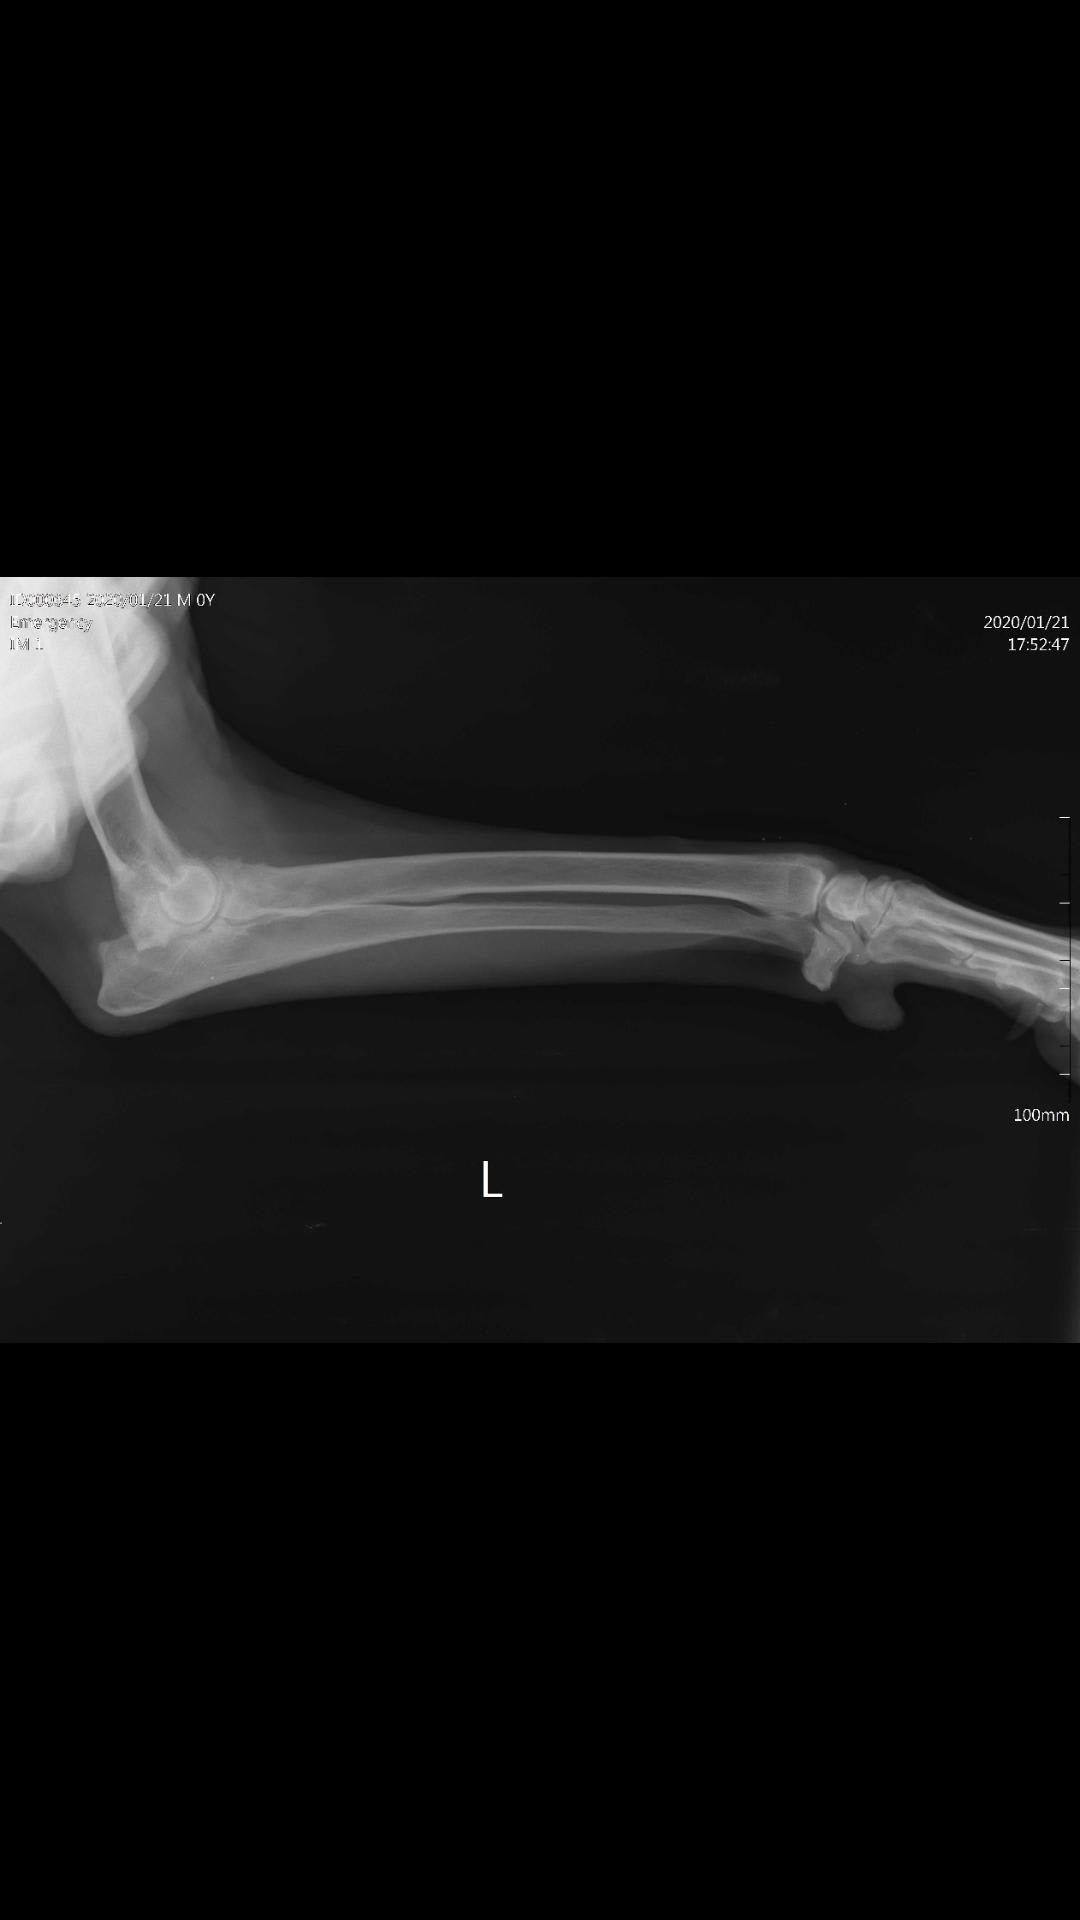

hi my dog has bern limping for almost a year he is in georgia (country) and unfortunatelly georgian unprofesional vets can't help us,he is 9-10 years ols german sheperd.i got today's x ray,can you plz tell me hats wrong with him?

Hello, sorry to hear about Rex. It does appear that he is having severe osteoarthritis of the elbow. This will directly limit his ability to move that arm and cause some obvious lameness. Unfortunately as seen by the radiographs, osteoarthritis is not reversible and thus managing his weight and activity will be the most fruitful with the goal focused on making him comfortable and not to make him not lame. There are some surgical procedures being explored that in the near future could offer a replacement of the elbow joint in dogs like Rex with severe elbow disease. I would recommend using joint supplements, anti-inflamamtories, and pain medications as necessary to keep him comfortable. Unfortunately, Rex may never be able to walk normally with how severe his arthritis int hat elbow is. You may discuss having Rex referred to an orthopedic surgeon for further evaluation and care. Hope this helps and best of luck.